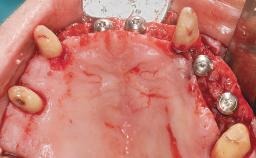

Conventional Loading of Eight Implants in the Maxilla and Final Restoration with a Full-Arch Gold-Ceramic FDP

A 35-year-old Caucasian female presenting with advanced periodontal disease involving both the maxillary and the mandibular dentition was referred for evaluation. The patient, a non-smoker in good general health, requested treatment for recurrent periodontal abscesses, tooth mobility, and discomfort during chewing, as well as restoration of her missing teeth with a fixed prosthesis to improve mastication and esthetics. All residual maxillary teeth exhibited plaque deposits, deep pockets, bleeding on probing, and class III mobility and were evaluated as hopeless. All residual mandibular teeth except tooth 37 could be maintained after periodontal therapy.

# of Implants 8

Type of Implants One-Piece

Bone Augmentation Horizontal|Staged|Vertical

Augmentation Materials Autogenous block(s)

Soft Tissue Grafting Staged